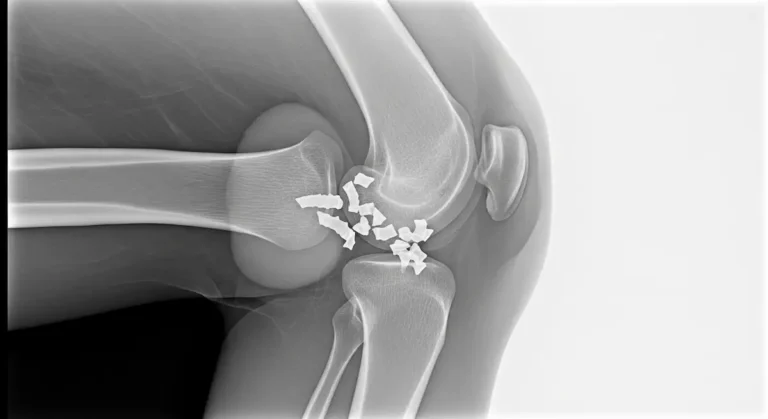

A síndrome de Osgood-Schlatter é uma dor irritativa no ponto em que o tendão patelar se ancora na tuberosidade da tíbia. Saltos, corridas e chutes aumentam a tração do quadríceps e inflamam essa área de crescimento. É comum em crianças…